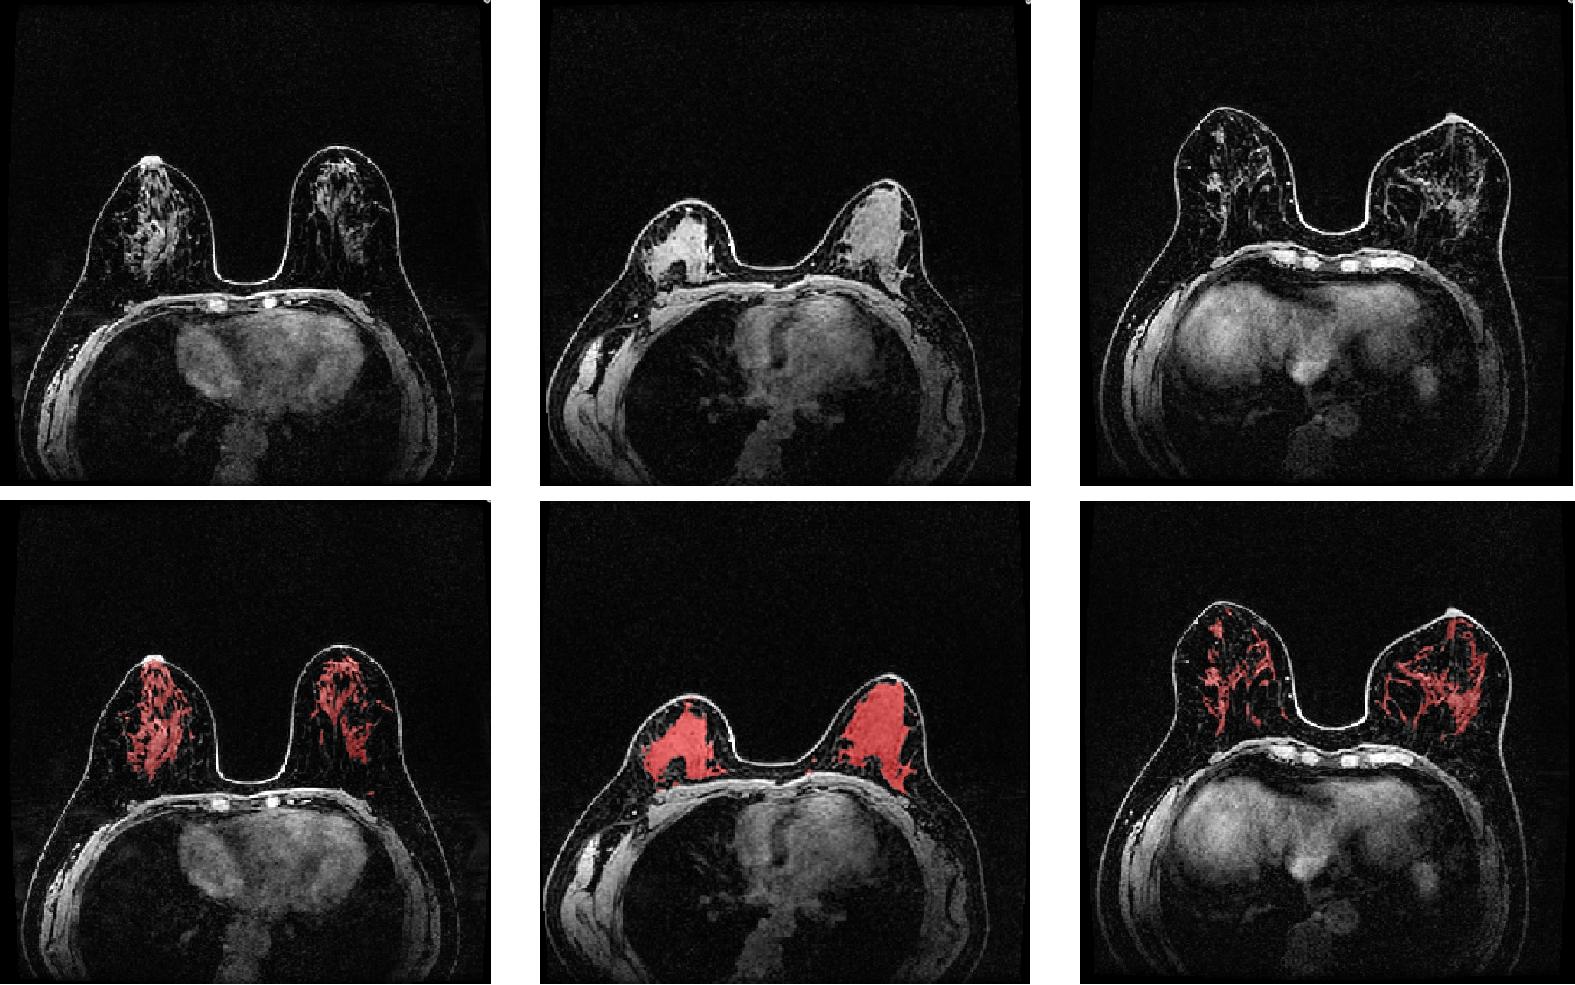

FGTSA toolkit is a Python package, which is able to detect/segment Fibroglandular Tissue regions and calculate relevant quantitative imaging biomarkers (e.g., background parenchymal enhancement, BPE) in breast MRI scans, which are highly associated with breast cancer risk, treatment response and prognosis.

FGTSA uses Fuzzy c-Means clustering (FCM) as a default method, which is a commonly used method for FGT segmentation. Note that, we are also developing other algorithms that will be released soon.

The enhancement of normal fibroglandular tissue observed at contrast-enhanced breast MRI is known as background parenchymal enhancement (BPE). The degree of BPE is typically assessed in four qualitative categories (minimal, mild, moderate, or marked) in clinical practice, which is required reporting during MRI interpretation in Breast Imaging Reporting and Data System (BI-RDS, fifth edition). FGTSA provides elaborate calculation for BPE report in percentage. The formular BPE expression is as follows:

$$BPE=\frac{\sum_{i=1}^{N}\frac{S_{1,i}-S_{0,i}}{S_{0,i}}}{N}$$